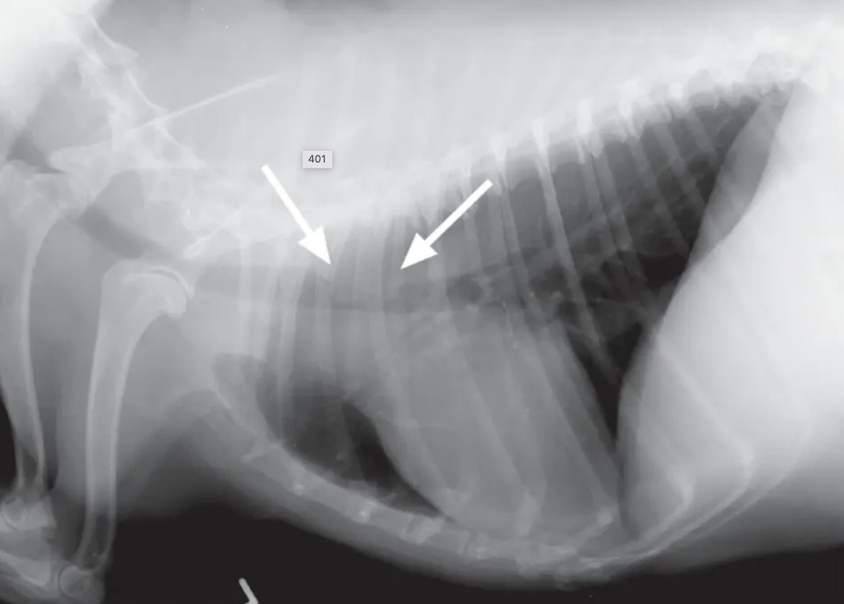

![]() | Mediastinum - abnormal shift - 여기서는 심장이 오른쪽으로 붙음 - 무기폐, 폐자름술, 폐종양일 때 발생 |

![]() | - 옆으로 몇 분 누워있었더니 무기폐 생긴 환자. - 무기폐가 생겨 심장이 왼쪽/오른쪽으로 틀어질 수 있음. - 섣불리 좌심비대로 평가하면 X |